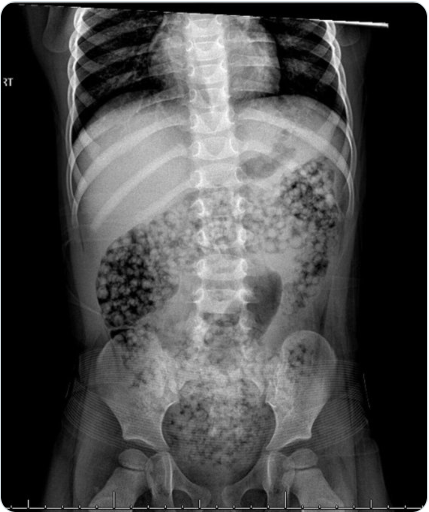

C Hoffman et al. J Pediatr Gastroenterol Nutr. 2024;78:448–449. Open Access! Orbeez ingestion: Successful medical management of1000 absorbent bead ingestion in a 3‐year‐old patient

“There is no consensus regarding optimal management in instances of Orbeez™ ingestion. However, a review of reported cases from 2021 indicated that of 43 cases of bowel obstruction secondary to water bead ingestions, two patients required endoscopic removal and the remaining 41 required surgical enterotomy or intestinal resection. We report a case of successful medical management following ingestion of over 1000 water beads…The patient was placed on a clear liquid diet and received a mineral oil enema with minimal passage of beads. She was then started on sennosides and erythromycin ethylsuccinate to help stimulate expulsion. Stools were closely monitored and revealed passage of greater than 1000 beads over the next 24 h.”